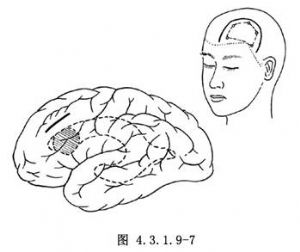

前角腫瘤以病側前額皮骨瓣入路開顱術爲宜。硬腦膜瓣基底翻向矢狀竇側。在運動區前額上、中回之間切開腦皮質和白質進入側腦室(圖4.3.1.9-7)。